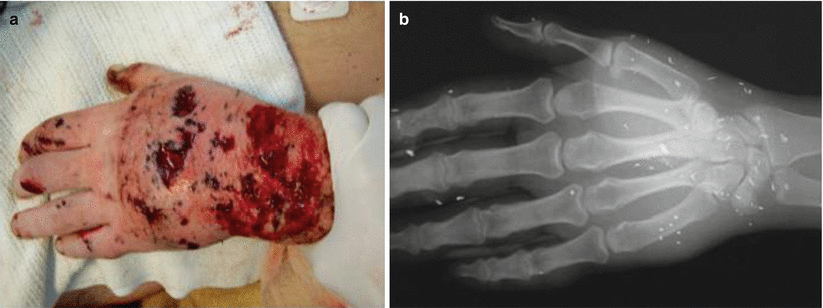

Fig. 71.3

(a) Hand injury with multiple fragmentations. (b) Plain x-ray of the hand